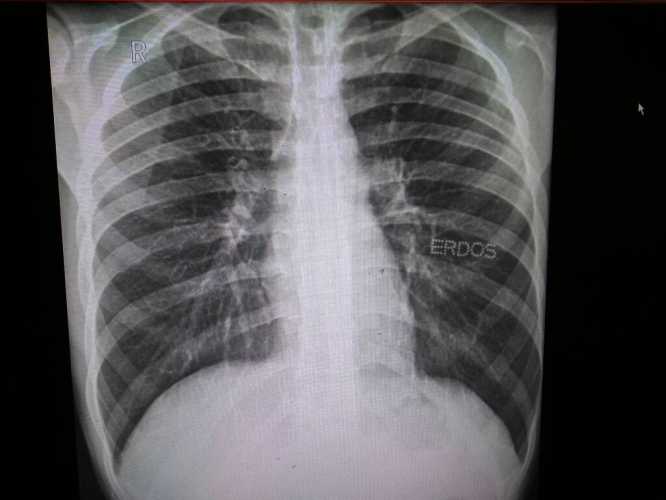

婴儿拍胸片辐射不大。

拍胸片是通过X线成像,确实有辐射。但现在医疗设备先进,一次胸片的辐射剂量很低。就像我家宝宝之前肺炎拍胸片,当时我也害怕辐射影响。医生说这点辐射对宝宝健康没啥大影响。

而且,拍胸片能帮医生快速发现肺部问题,比如肺炎、肺部异物等。相比疾病对宝宝的危害,偶尔拍一次胸片的辐射可以忽略不计。

要是宝宝有相关疾病,需要拍胸片,宝妈们别太担心辐射。不过要是能不拍,肯定尽量不拍。但真有必要,也别因为担心辐射而耽误诊断和治疗。